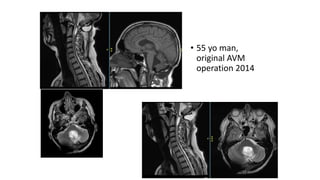

• 55 yo man,

original AVM

operation 2014

AHV6121 • 55 yoman, original AVM operation 2014